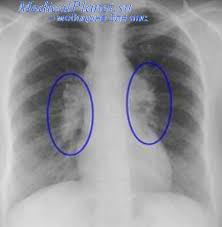

Возникновение фиброза лёгких могут провоцировать:

- Профессиональные заболевания легких;

- Ревматоидный артрит;

- Системная склеродермия

- Инфекции (пневмония, туберкулёз).

В результате фиброза лёгких может развиться хроническая дыхательная недостаточность, пневмония и другие осложнения.

Первыми симптомами фиброза легких является отдышка, кашель, бледность кожи. Далее появляются: повышенная утомляемость, признаки сердечной недостаточности: отёки ног, набухание шейных вен.